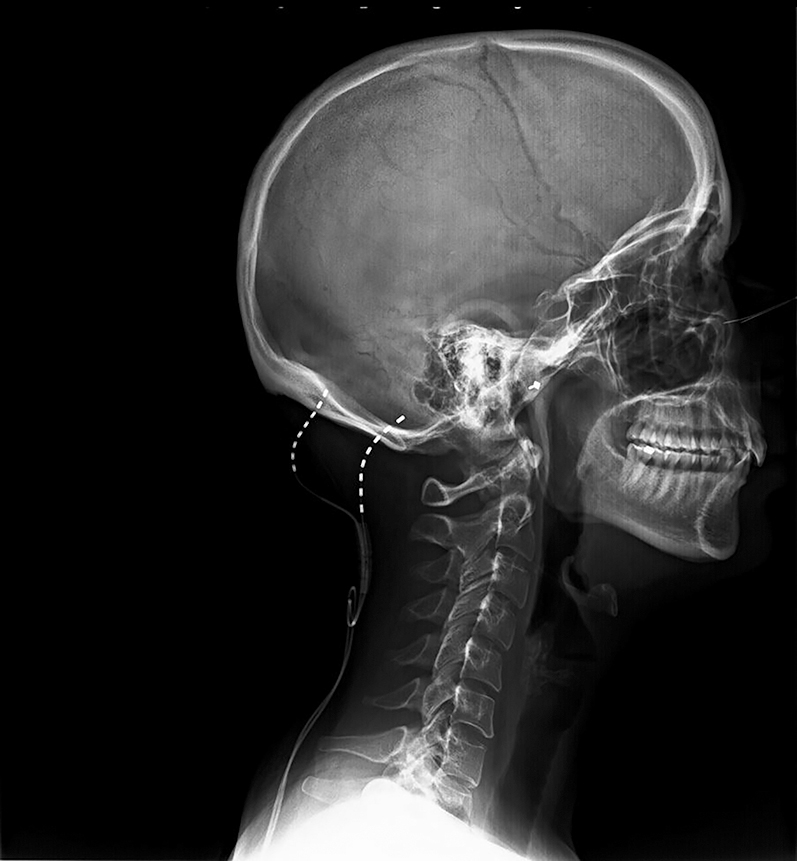

Twenty nine-year-old patient referred due to bilateral Arnold neuralgia and long-term cervicogenic headache. She was refractory to pharmacological treatment and repeated minimally invasive techniques on dorsal root ganglia and terminal branches of C2C3. According to previous background, the patient was scheduled for subcutaneous ONS. Under monitored sedation, bilateral occipital subcutaneous leads implant was performed. Two 90 cm Vectris Surescan electrodes, model 977A275 (Medtronic, Minneapolis, MN, USA), were placed with the introduction site at the level of C1C2. The tips of the leads in correspondence to the mastoid process were checked, the electrodes position overlapping with the patient’s pain area was monitored, without motor response to the cranial musculature that could lead to painful muscle stimulation [26] (in this phase the sedation was temporary interrupted to receive a functional feedback from the patient). Once adequate coverage was obtained of the symptomatic area, leads anchoring was done at the entry point , in the cervical paraspinal fascia using the Injex Bumpy lead anchor, model 97791 (Medtronic, Minneapolis, MN, USA). Strain-relieving, subcutaneous lead loops were used to absorb the stress of cervical movements, and minimize the risk of lead migration, as it is shown in Figures 1 and 2.

Lateral fluoroscopy view at initial placement with leads entry point at C1.

Figures 1 and 2 show the final position of the implanted leads.